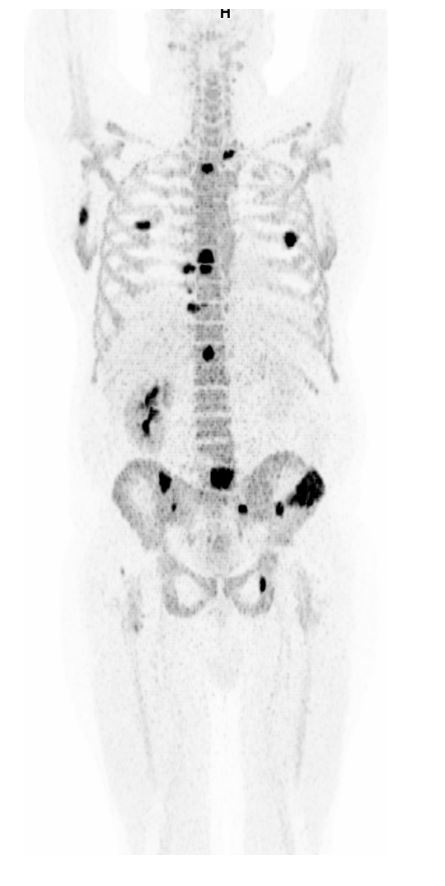

Knogle-PET (Natrium-Fluorid-PET), der viser metastaser udbredt i skelettet.